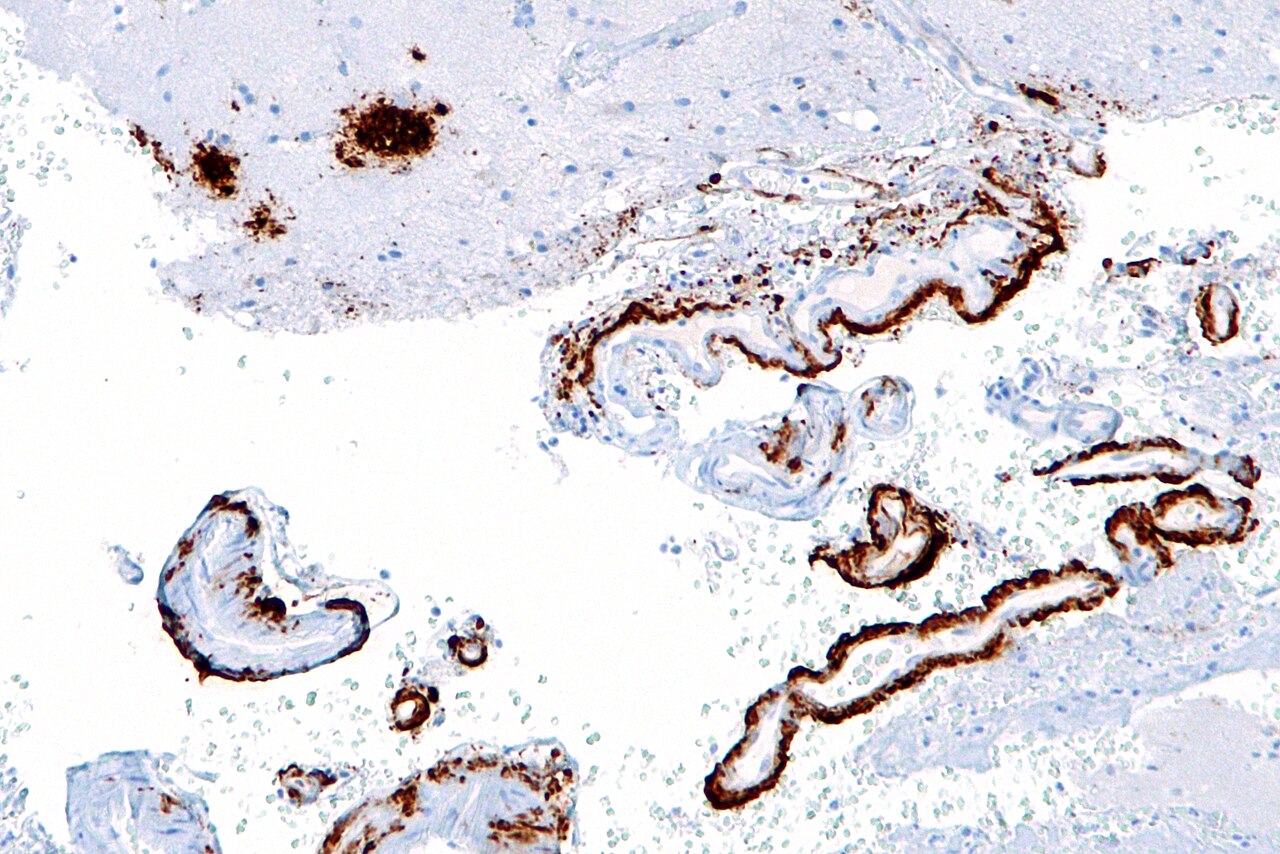

Pro Alzheimerovu chorobu je charakteristická tvorba amyloidu-beta (hnědý) ve formě plaků v mozkové kůře. Kredit: Nefron, licence CC BY-SA 3.0